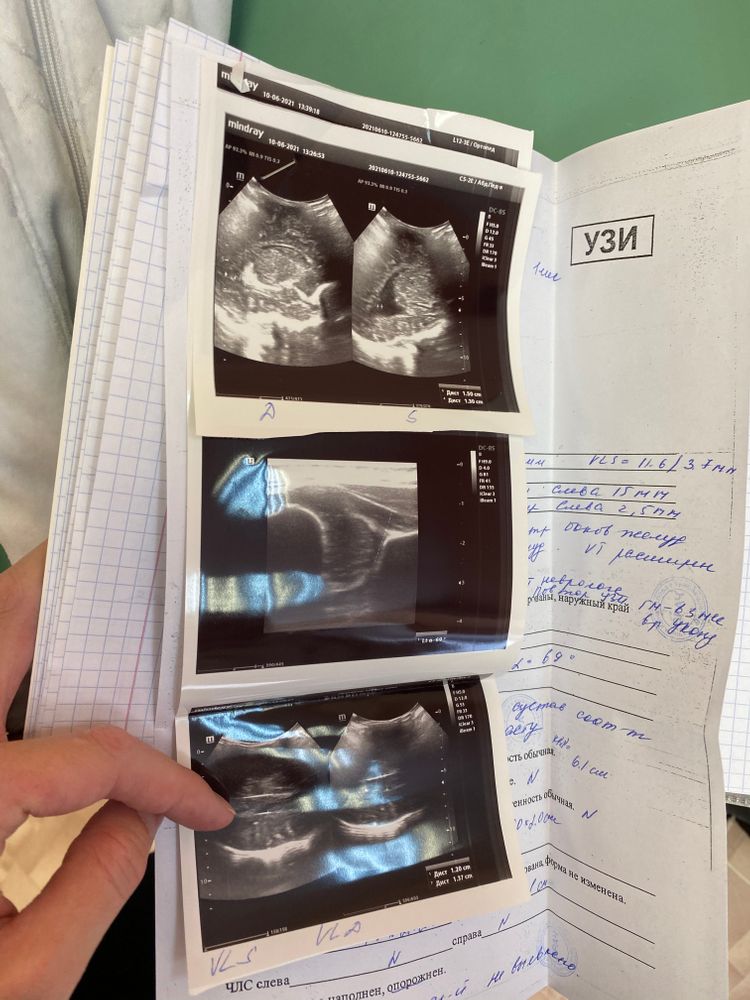

Асимметрия боковых желудочков

Изображение

Всем привет ! Делали узи в 1 мес , сказали , что есть асимметрия боковых желудочков .

не могу понять сколько мм эта асимметрия по заключению .

кто сталкивался ?